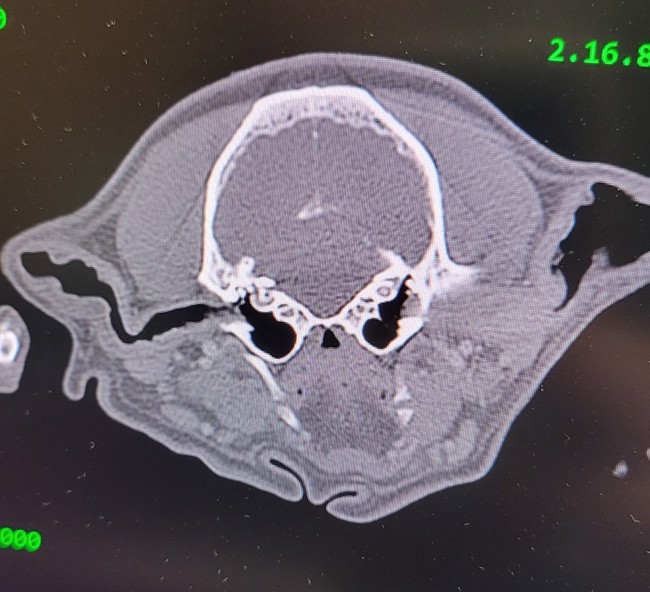

Our state-of-the-art CT scanner provides highly detailed, three-dimensional images of the ear structures in dogs and cats, allowing for a more accurate diagnosis and treatment plan for otitis (ear infections) and other ear conditions.

Unlike traditional X-rays, CT imaging offers clear visualization of the ear canal, bulla (middle ear), and surrounding structures, helping to identify fluid buildup, inflammation, masses, polyps, or bone involvement that may not be visible through standard examination methods.